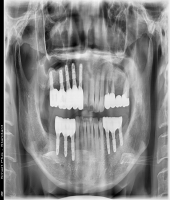

| ● 진료과목 : [임플란트] 치주환자의 임플란트 보철치료

| ● 내용 : 50대 치주환자의 임플란트치료. |